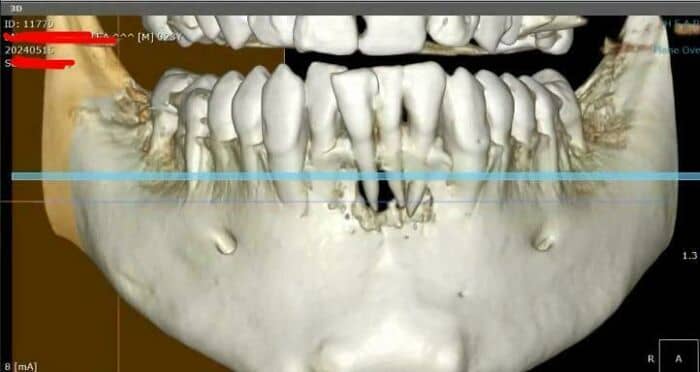

#1 My Mandible Has A Hole In It

First of all no, it wasn’t caused by a traumatic event. It was a big infection and yes it was painful. Second thing is that a year ago i was still under chemotherapy and my doctor said that may aggravated the infection because chemo really weakened my immune system and my body. My oncologist said that even though my immune system was very weak that shouldn’t affect the bone, especially that much. Everything is healing now and I’m 9 months cancer free.